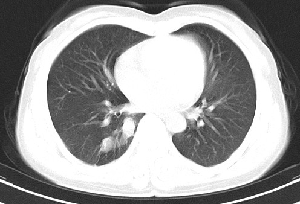

下叶后基底段近膈面见一椭圆形密度均匀增高的阴影,边界较清,其长轴指向内后方,考虑肺隔离症,建议增强扫描了解与主a联系!

右下肺隔离症有可能,另外可能是炎性假瘤

1\\没有什么病史吗,没有看到与腹主动脉有联系呀,肺隔离症不是太象

2\\如果没有明确临床体征,炎性假瘤到是可以考虑

右下肺隔离症考虑,不除外炎性假瘤,建议增强。